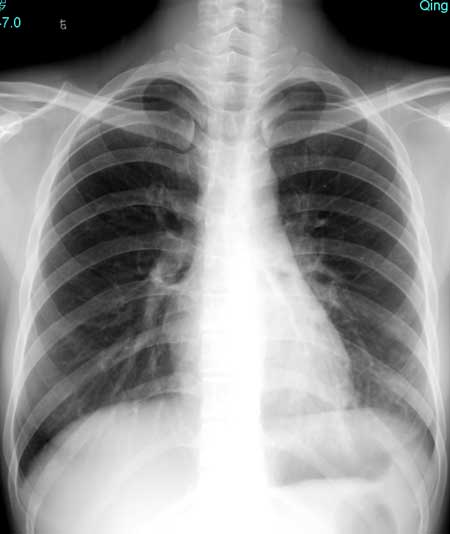

以下是引用pujunzhi在2008-7-1 20:03:00的发言:[br]支持楼主意见!两肺继发性肺结核伴多发空洞形成。